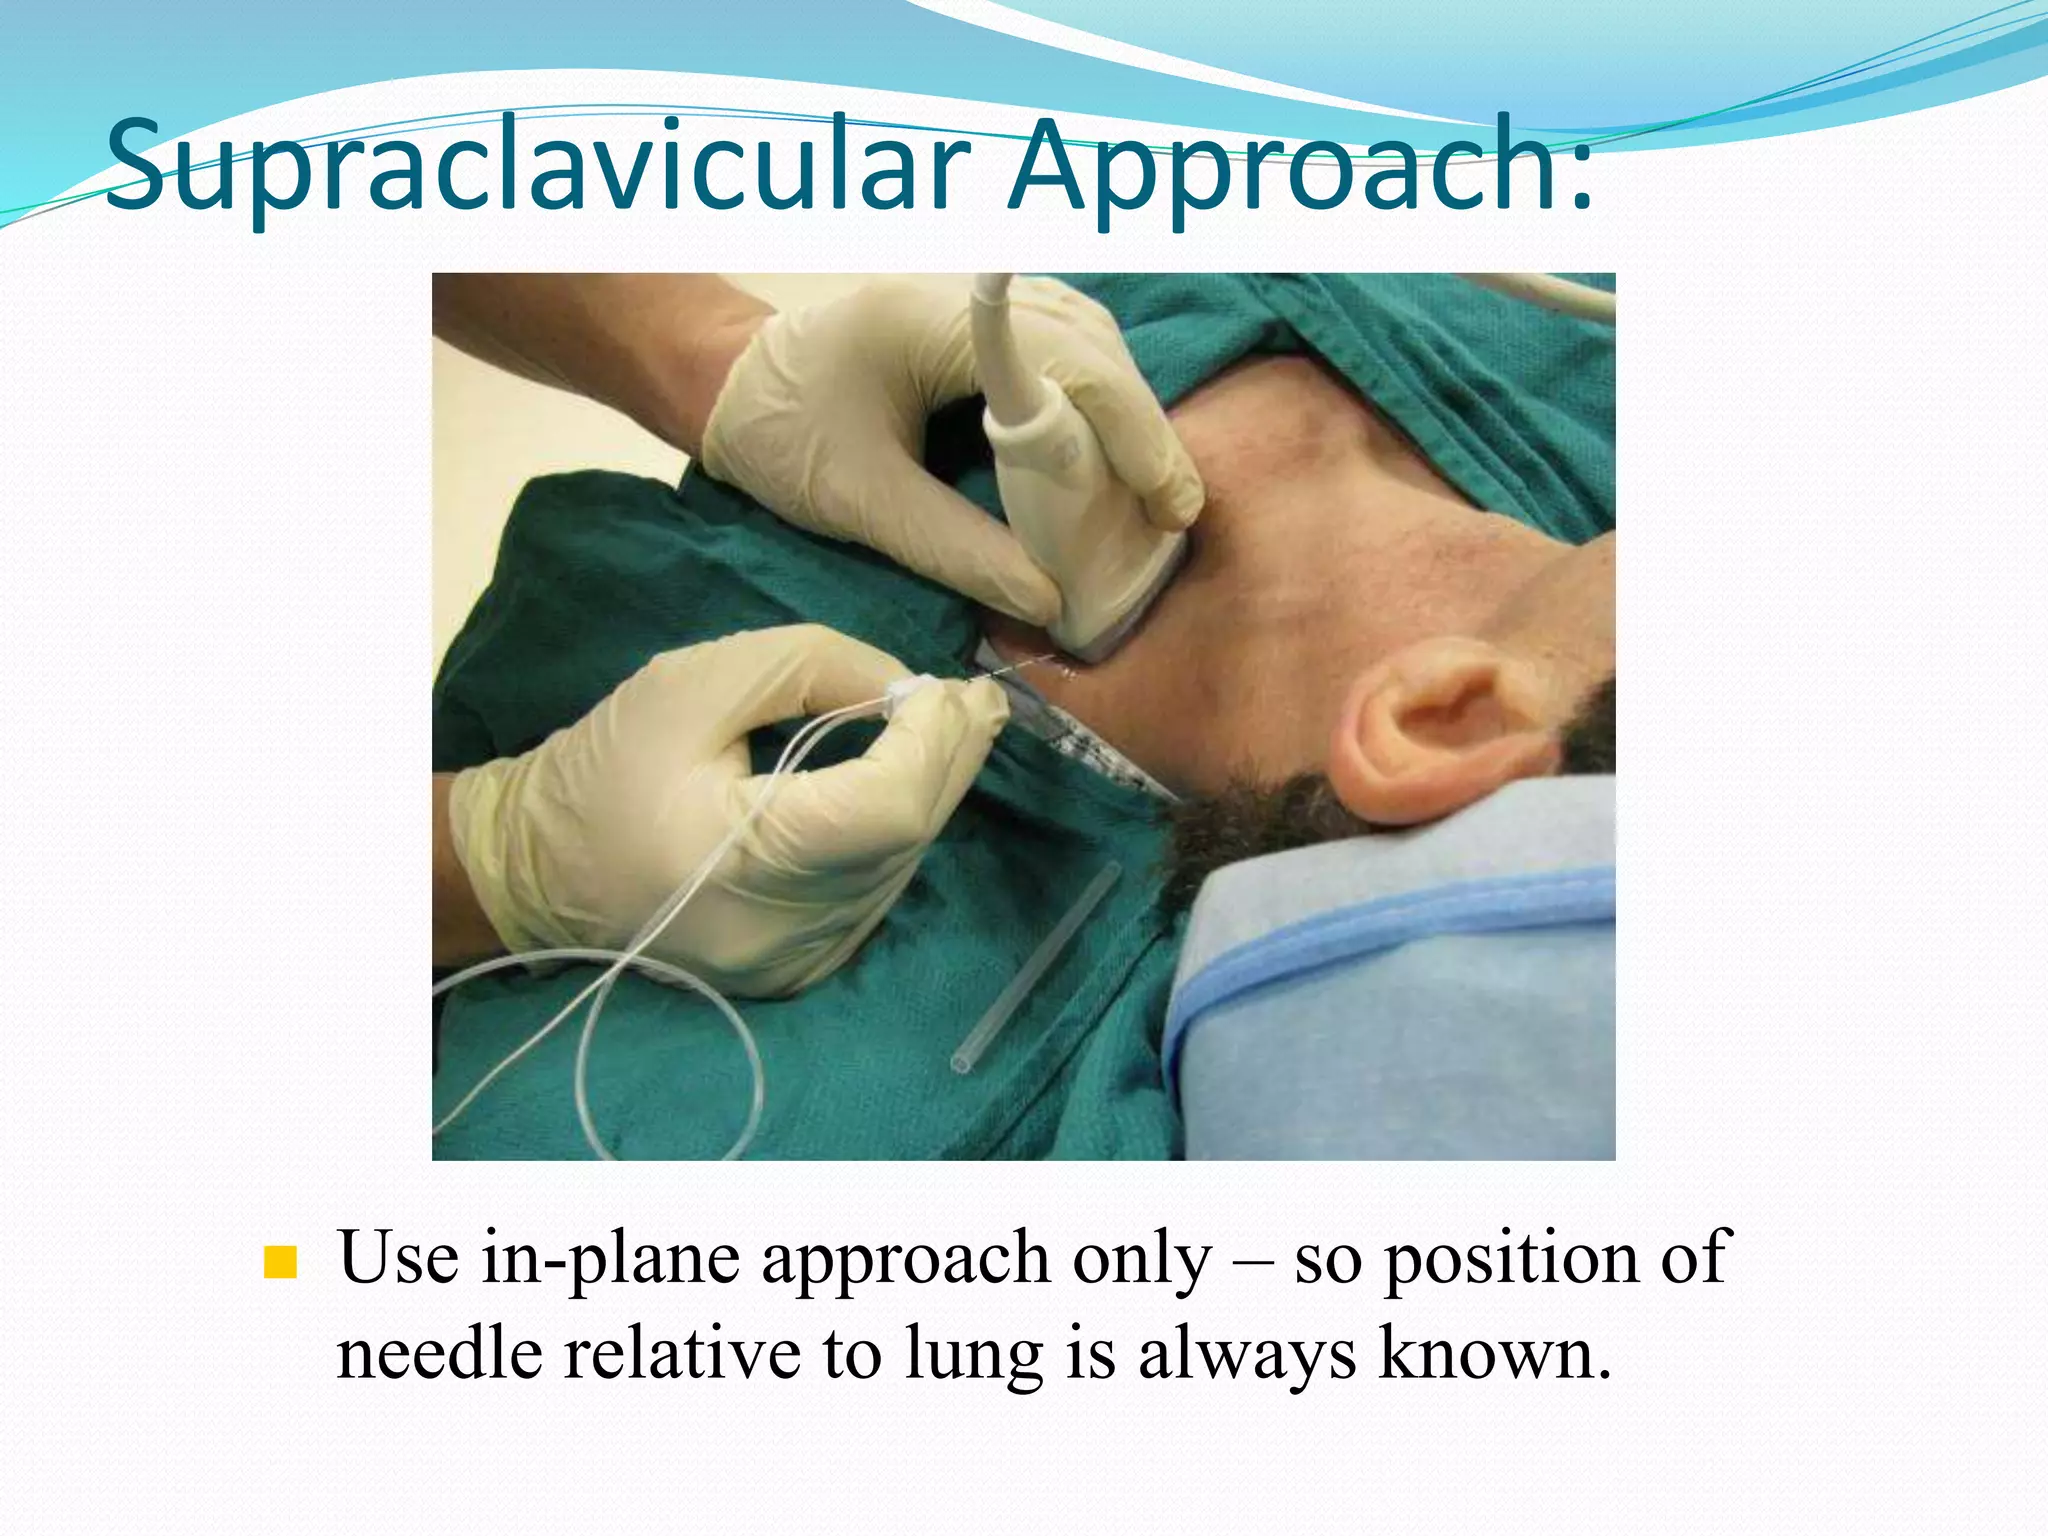

This document provides an overview of brachial plexus anatomy and techniques for brachial plexus nerve blocks. It begins with a description of the brachial plexus formation from cervical and thoracic nerve roots and its branching pattern. Four main approaches for brachial plexus nerve blocks are described: interscalene, supraclavicular, infraclavicular, and axillary. Details are provided on the anatomy and techniques for performing interscalene and supraclavicular brachial plexus blocks. Ultrasound guidance is discussed as an advancement which allows real-time visualization of needle and nerve. Complications are also summarized.